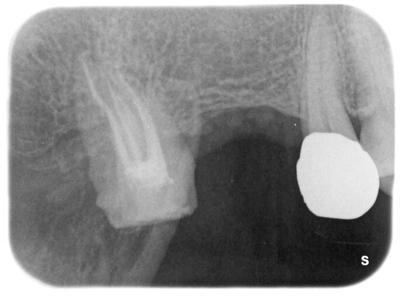

友川_桂子_ライトボックス(1)_口腔内_20210208_154023.jpg

根管充填後の写真。

きれいに充填できている。

ここまでの治療回数2回、トータル治療時間2時間。